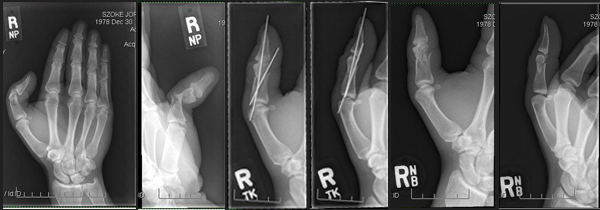

On Sunday, August 10th, Jordan Szoke, defending Canadian Superbike Champion and the defending Canadian National Observed Trials Champion, suffered multiple fractures of his right thumb. Resulting in surgery to repair the extensive damage, ending his bid for both of his defending championship titles. Szoke’s season came to a screeching halt.

Szoke had the pins removed that were placed in his thumb during surgery to hold the proximal phalange bone and his distal phalange bone together on Sept 2nd by Dr Richard Inman. The extensor tendon was also reattached during the procedure.